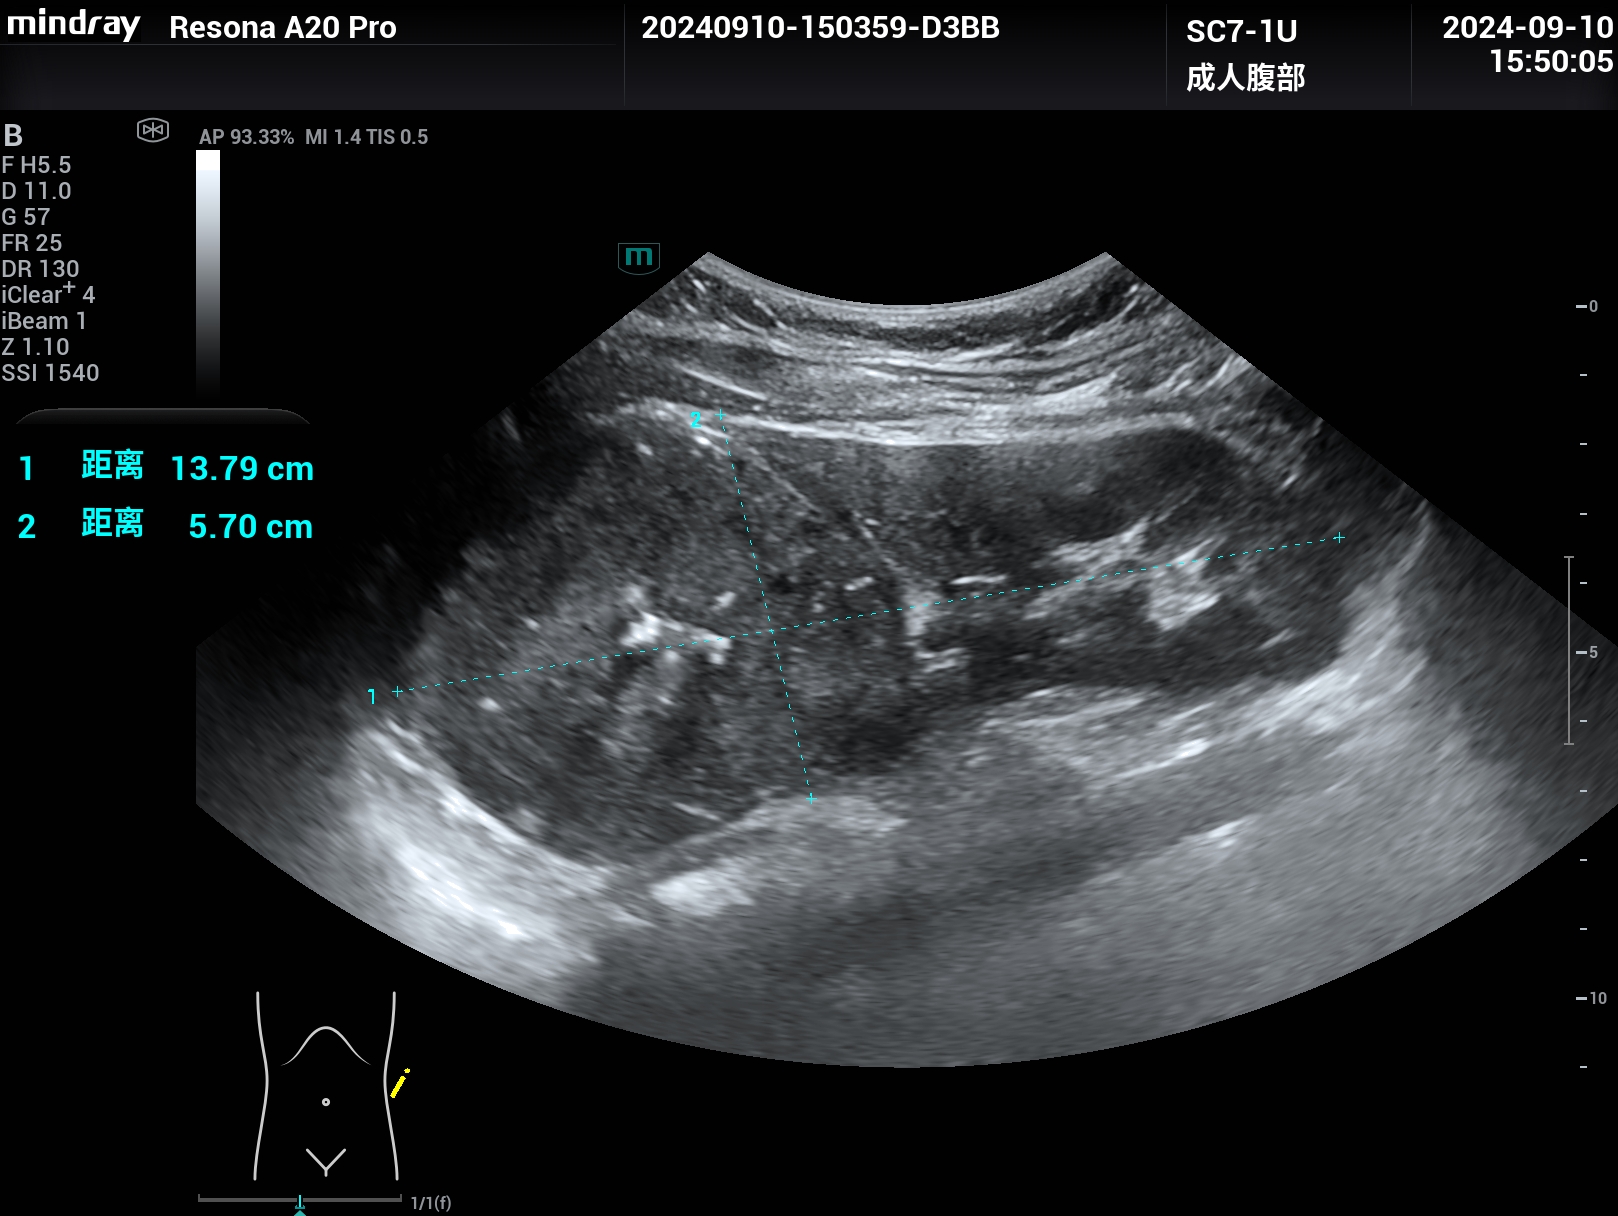

肾脏癌性大包块,扩展成像,腹部探头变成腔内探头的超宽视野,但分辨力依然清晰,超高端Resona A20

肾脏癌性大包块,腹部探头扩展成像,腹部探头成腔内探头的超宽视野,但分辨力依然清晰。